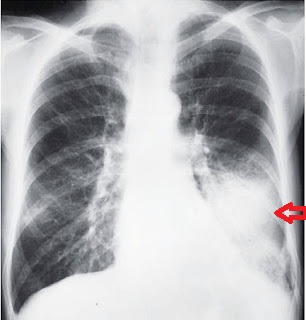

bronchi. There is lot of overlap of bronchopulmpnary segments on a PA view of

chest but they project separately on a lateral view. Their approximate location

as seen on frontal and lateral radiographs is illustrated

Radiographic density of the two lungs is

symmetrical on a well-taken PA film. If the patient is rotated, the hemithorax

closer to the film appear more radiodense. Both PA and lateral views are

necessary to localise in one or more of the pulmonary segment. Since the normal

bronchi are not visualised in the peripheral lung fields, it is difficult to

make out the boundary of different pulmonary segment on plain radiograph of the

chest.